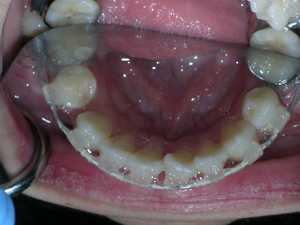

Here are the porcelain braces applied.